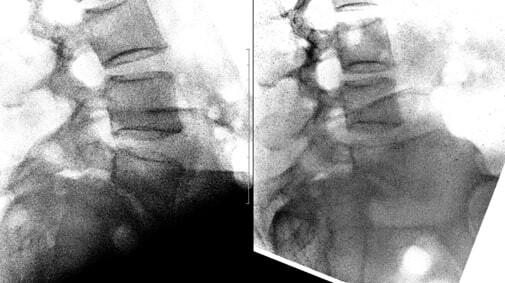

Пациент делает рентгеновские снимки не просто стоя, а в максимальном наклоне вперед и назад. Это показывает, как ведут себя позвонки в движении. Смещение, которое было незаметно в статике (на МРТ или КТ), может явно проявиться при сгибании-разгибании.

Бывает, что спондилолистез, четко видимый на МРТ, оказывается стабильным на функциональных снимках — то есть позвонки не «ездят» друг относительно друга при движении. И наоборот, вроде бы небольшая проблема на МРТ может маскировать серьезную нестабильность.

Именно сочетание жалоб пациента и данных функциональной рентгенографии часто становится решающим аргументом в пользу операции, например, для установки системы стабилизации (металлофиксации).